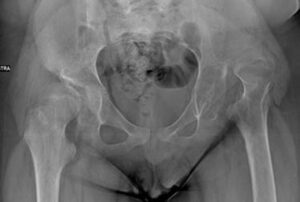

Hip dislocation and subluxation are fairly common conditions in children with Cerebral Palsy , with a frequency ranging from 15-20% to 75% in the most severely affected patients. This dislocation is not present at birth, but develops progressively over the years .

A series of factors ( spasticity and retraction of the muscles, especially the adductors and iliopsoas, altered proprioception and inadequate muscle control, prolonged adduction postures of the patients, lack of weight bearing, etc. ) have been called into question to explain the process by which the head of the femur progressively moves away from its seat until it dislocates completely, and marked anatomical alterations are determined (intratorsion of the femur, valgus of the femoral neck, slippage of the acetabulum, tendon retractions, pelvic obliquity, etc.).

- the severity of the dislocation (evaluating specific radiographic parameters)